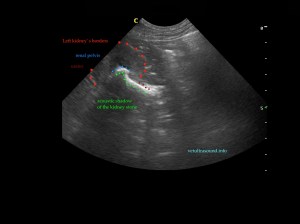

Ευρήματα: Παρουσία λίθου στην πύελο του αριστερού νεφρού ο οποίος καταλάμβανε όλη την κοιλότητά της και εκτεινόταν στο πρώτο τμήμα του ουρητήρα. Ο λίθος προκαλούσε ήπια διάταση του πυελοκαλυκικού συστήματος και του ουρητήρα. Αντίστοιχα στον δεξιό νεφρό βρέθηκε λίθος ο οποίος εντοπιζόταν μόνο στην κοιλότητα της νεφρικής πυέλου. Στην ουροδόχο κύστη βρέθηκε μικρή παρουσία ιζήματος.